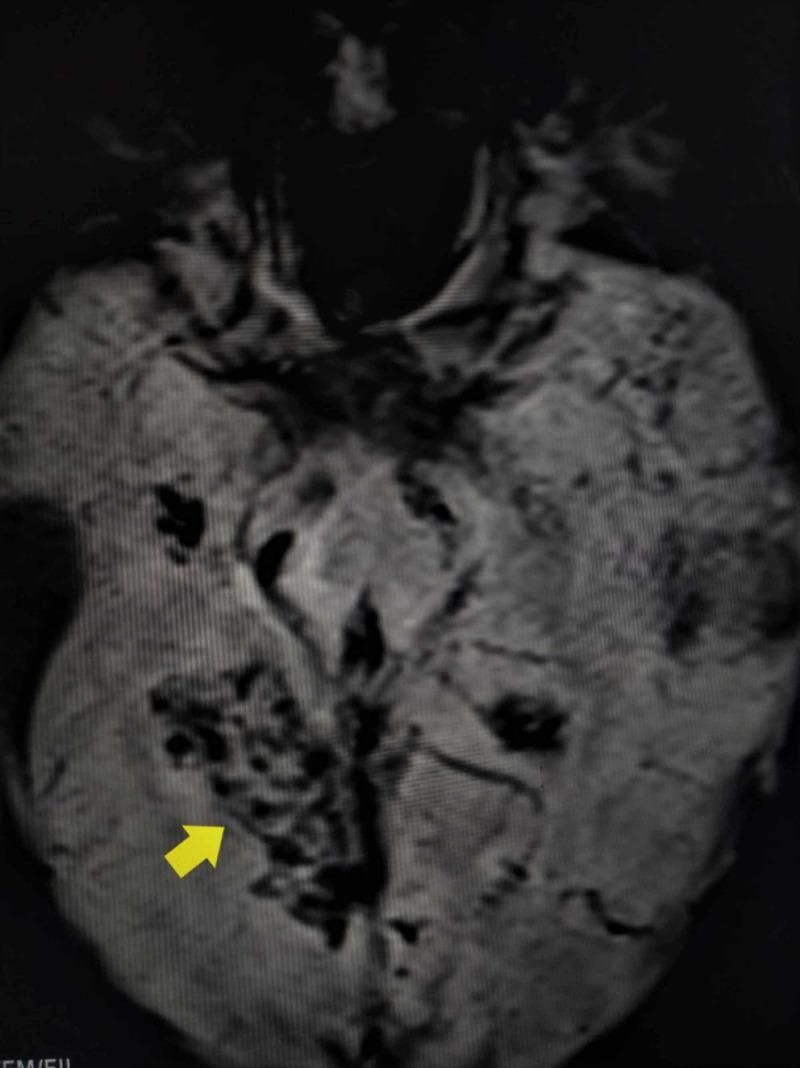

Autoimmune-associated vasculitis is related to conditions like granulomatosis with polyangiitis (GPA) and eosinophilic polyangiitis with granulomatosis (EGPA), among many others. An unlikely scenario is patients with the above conditions presenting with ischemic strokes before any renal or pulmonary pathology. These conditions are associated with increased antineutrophillic cytoplasmic antibodies (C-ANCA) levels in the blood, and its decline after treatment is directly proportional to the recovery of the patient. We present a case of a previously healthy 38-year-old male patient who presented with acute/subacute ischemic stroke with elevated C-ANCA levels; his MRI brain images revealed multiple posterior circulation infarcts with hemorrhagic transformation. With pulse steroid therapy, he had significant improvement in neurological functions. This case report highlights the importance of maintaining a high degree of suspicion and providing early treatment for autoimmune strokes in young patients with no clear etiology for such a presentation.

自身免疫相关血管炎与多种疾病相关,如肉芽肿性多血管炎(GPA)和嗜酸性肉芽肿性多血管炎(EGPA)等。一种不太可能出现的情况是,患有上述疾病的患者在出现任何肾脏或肺部病变之前就发生缺血性中风。这些疾病与血液中抗中性粒细胞胞浆抗体(C-ANCA)水平升高有关,治疗后其水平下降与患者的恢复直接相关。我们报告一例38岁既往健康的男性患者,他因急性/亚急性缺血性中风就诊,C-ANCA水平升高;他的脑部MRI图像显示多个后循环梗死灶并伴有出血转化。经过脉冲类固醇治疗,他的神经功能有显著改善。本病例报告强调了对于无明确病因的年轻自身免疫性中风患者保持高度怀疑并提供早期治疗的重要性。